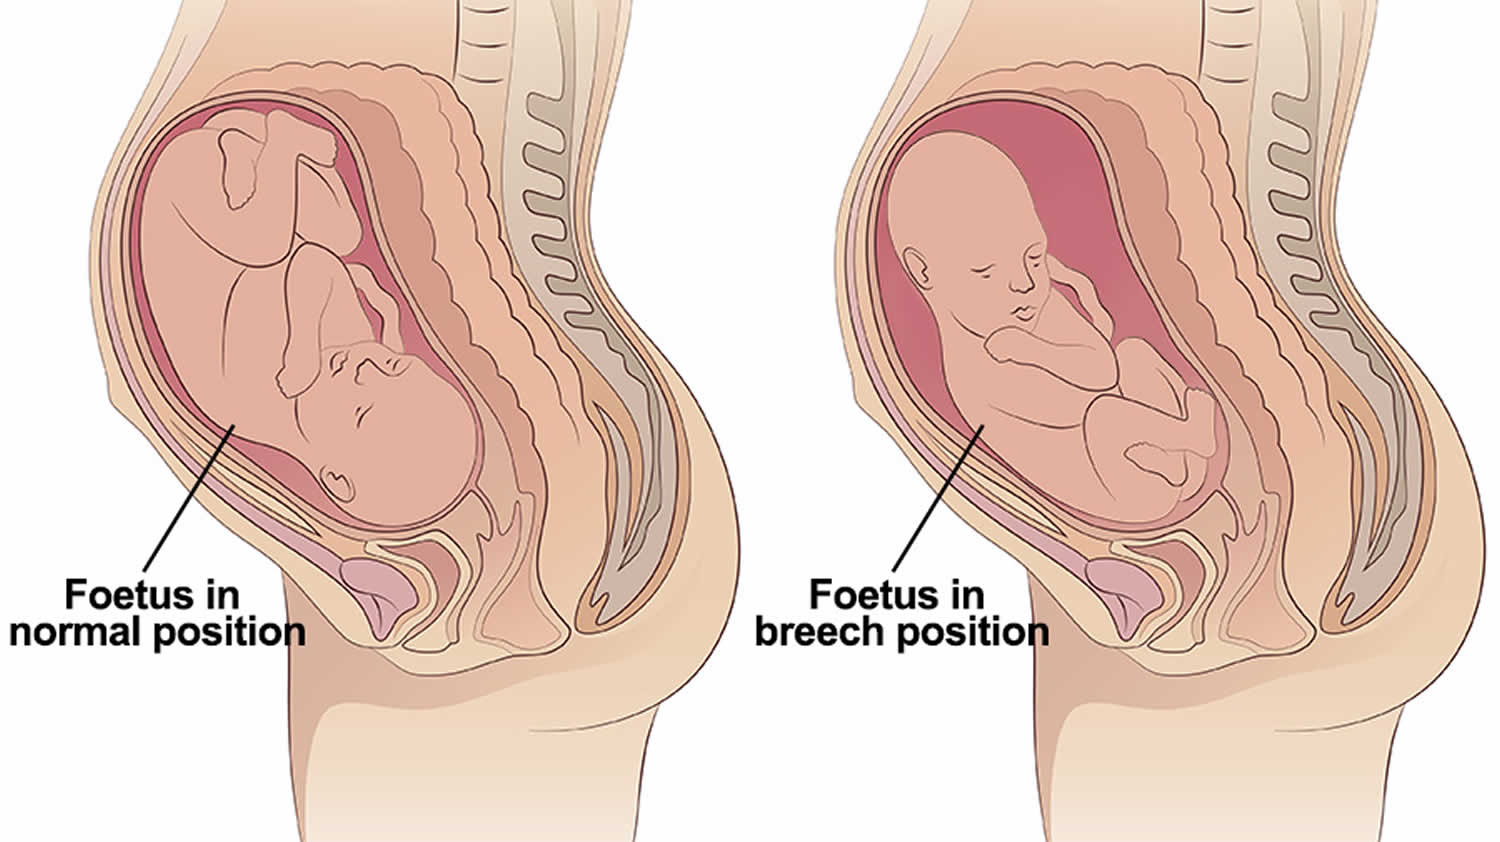

Во время беременности, положение плода имеет большое значение для мамы и малыша. Одним из типичных положений является продольное предлежание головное. В этом положении голова малыша находится внизу, а ножки - наверху. Это положение достаточно распространено и предпочтительно для естественных родов.

Breech.webp)

Живот с ягодичным предлежанием

Longitudinal Lie and Cephalic position of child